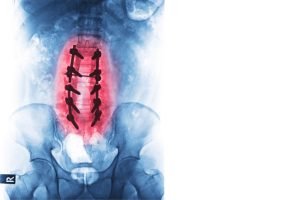

يتم دمج وتثبيت الفقرات القطنية مع إزالة الجزء الفارغ الذي يشغله الغضروف بين الفقرات ليتم منع الحركة بين الفقرات وتعتمد العملية على آلية شفاء العظام بشكل طبيعي بحيث يقوم دكتور اسلام الأجهوري بوضع مادة عظمية أو مادة شبيهة بالعظام الطبيعية في المكان الفاصل بين الفقرات المراد تثبيتها ويتم التثبيت باستخدام زراعة الشرائح، والمسامير، والأقفاص التي تتوافق حيويا مع الجسم من لحماية الرقع العظمية حتى تلتئم و يتم تحقيق الاستقرار والثبات في حركة العمود الفقري حتى يتم الالتحام و الشفاء.

- يقوم الجراح بوضع طعم عظمي اصطناعي بين الفقرتين، ثم وضع المسامير والشرائح المناسبة

- إذ يختلف شكل مسامير تثبيت الفقرات على حسب حالة ونوع الفقرات المصابة. تساعد المسامير والشرائح على تثبيت الفقرتين ببعضهما البعض، كي تلتئم الفقرتين بشكل طبيعي وتصبح غير متحركة